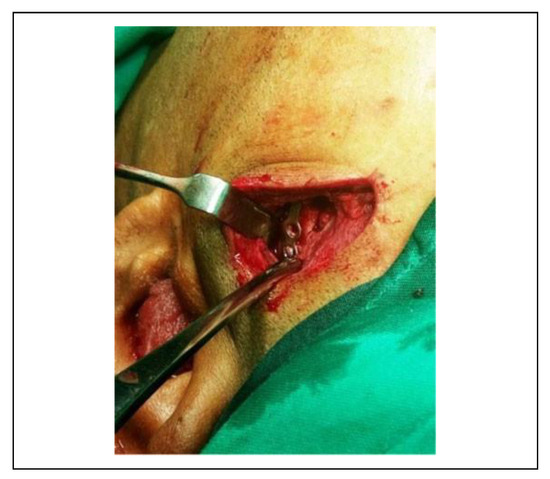

![]() |